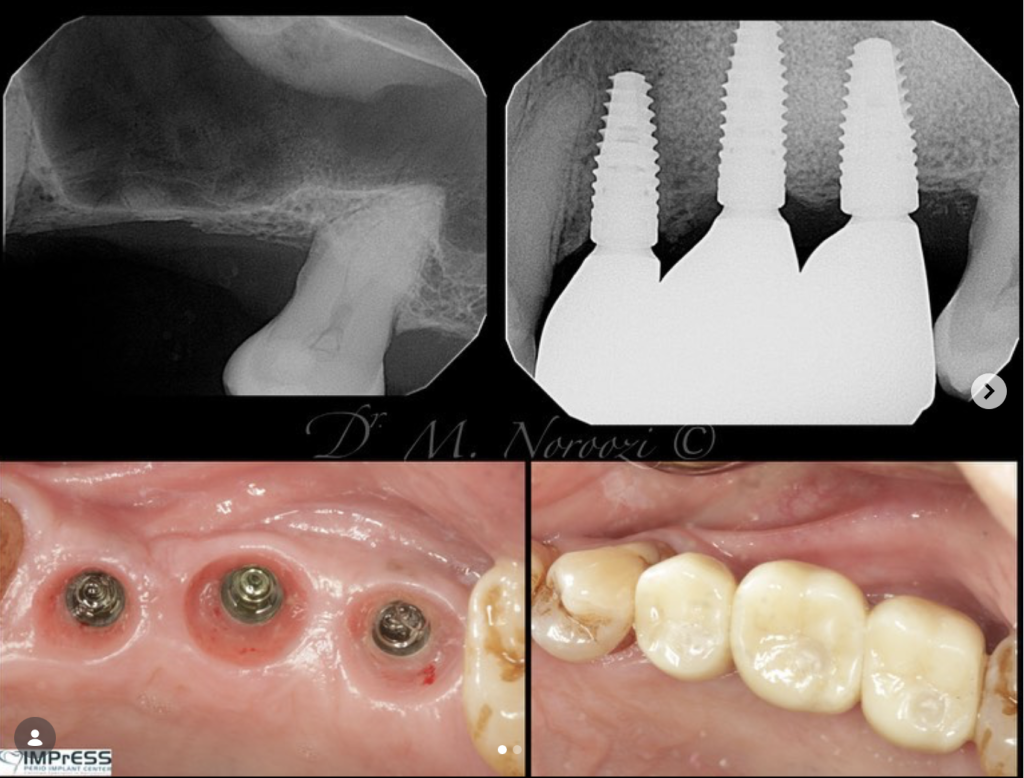

Our Specialists in IMPrESS Perio Implant Center have undergone extensive training in sinus lift surgery and have developed tremendous experience and skills over years to safely perform the sinus lift surgery with predictable treatment outcome.

Dr. Noroozi utilizes the most advanced technologies such as Piezosurgery to make your sinus lift surgery safer, more effective and comfortable for you.

Our specialist is commonly using proteins called growth factors to help the new bone harden faster. Platelet-rich plasma, which contains the growth factors, is taken from your blood before surgery and mixed with the graft that is placed into your sinus. Human-recombinant bone morphogenetic protein is an engineered protein that is now available. It stimulates bone formation without grafting. The U.S. Food and Drug Administration has approved its use during a sinus lift procedure.